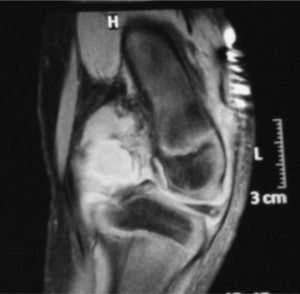

Nine days after admission, an MRI was performed which showed a moderate collection in the joint cavity, mainly in the intercondylar notch and showing contrast uptake compatible with synovial proliferation (Fig. 1). In the back of the left femoral condyle, we identified a small lytic lesion of approximately 7mm×5mm in diameter, associated with a collection that had peripheral contrast uptake, compatible with small bone inflammation. A CT was performed within 20 days, and a 6-mm lytic lesion was seen in the posterior aspect of the medial femoral condyle, with involvement of the cortical bone without any periosteal reaction observed (Fig. 2).